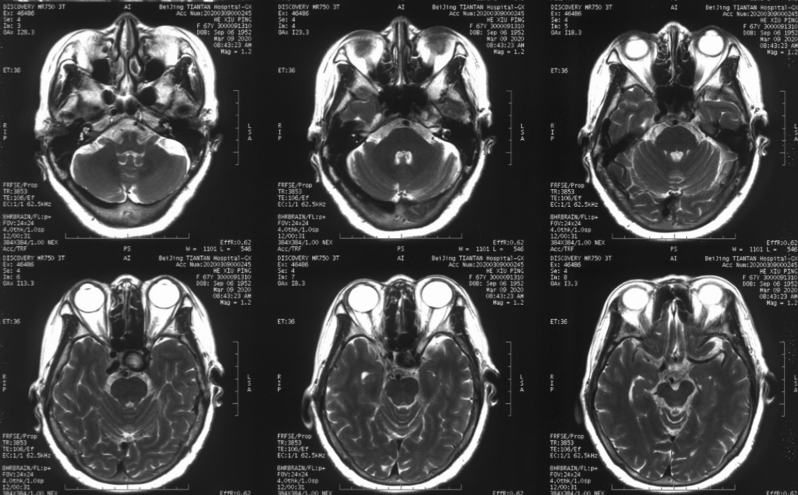

造影见左侧颈内动脉海绵窦段巨大动脉瘤,瘤体远端海绵窦水平段血管狭窄,眼动脉段血管扩张,左侧A1段缺如

本例患者动脉瘤位于海绵窦段,眼动脉段血管同时存在一定扩张异常,患者无明显高血压病史,从出血角度而言该患者相对出血风险并非极高。但根据核磁情况,尽管该动脉瘤位于海绵窦段,但已经有一部分瘤体突入颅内,一旦发生破裂出血,有一定可能进入蛛网膜下腔。且患者近期出现头晕及单眼黑朦,考虑与血流瘀滞于动脉瘤内有关。核磁上同样也可以看到瘤壁大量的血栓沉积,未来发生脑梗死的风险较大。此外,家属与患者对疾病的恐惧与治疗的决心也是我们最终决定施行手术治疗的原因之一。